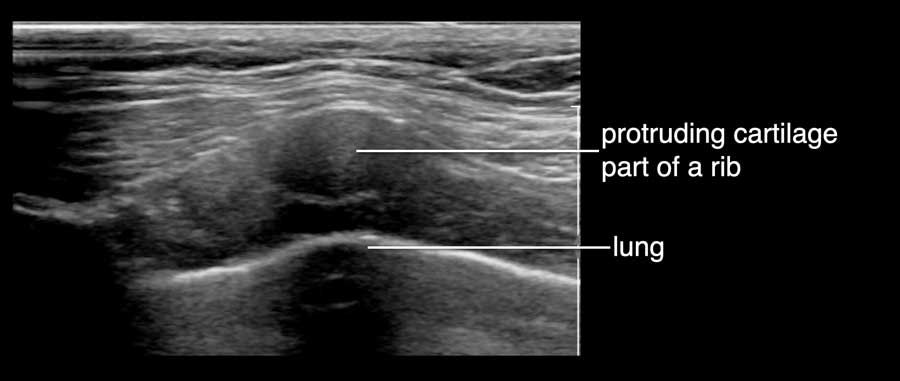

Một xương sườn nhô ra có thể tạo thành một khối cứng lồi lên, dễ nhầm lẫn với khối u vú.

Bệnh nhân này than phiền về một khối cứng đau trong vú.

Trên siêu âm, ghi nhận hình ảnh khớp sụn-xương sườn nhô ra.

Đây là vị trí tiếp nối giữa phần xương đã vôi hóa của xương sườn và phần sụn.

Các vôi hóa thường có thể được quan sát thấy trong phần sụn, như trong trường hợp này.

Video này minh họa hình ảnh sụn xương sườn bình thường.

Bằng cách xoay đầu dò, có thể thấy xương sườn là một cấu trúc chạy dọc, nằm phía trước phổi và phía sau cơ ngực.